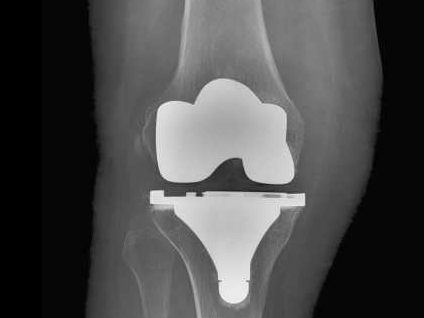

Les composants d'une Prothèse Totale de Genou

Cette intervention consiste à remplacer l’articulation du genou par des composants artificiels qui reproduisent l’anatomie initiale du genou. Le type d’implant doit être adapté à chaque cas particulier, en ce qui concerne sa forme, sa taille, la nature des matériaux entrant dans sa composition, son revêtement extérieur et la technique chirurgicale à employer.

Généralement, une prothèse de genou se divise en trois parties : un insert fémoral, une embase tibiale surmontée d’un polyéthylène et un resurfaçage de la rotule par un polyéthylène. Les composants sont le plus souvent fixés par du ciment.

La prothèse que nous mettons en place est un implant en alliage CrCoMo (implant fémoral) et titanium (implant tibial).